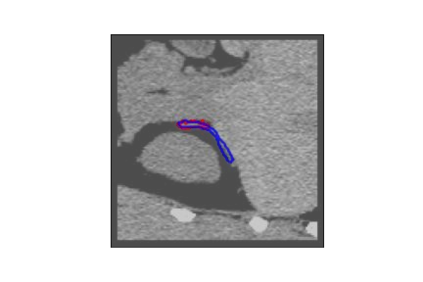

The human annotations are imperfect, especially when produced by junior practitioners. Multi-expert consensus is usually regarded as golden standard, while this annotation protocol is too expensive to implement in many real-world projects. In this study, we propose a method to refine human annotation, named Neural Annotation Refinement (NeAR). It is based on a learnable implicit function, which decodes a latent vector into represented shape. By integrating the appearance as an input of implicit functions, the appearance-aware NeAR fixes the annotation artefacts. Our method is demonstrated on the application of adrenal gland analysis. We first show that the NeAR can repair distorted golden standards on a public adrenal gland segmentation dataset. Besides, we develop a new Adrenal gLand ANalysis (ALAN) dataset with the proposed NeAR, where each case consists of a 3D shape of adrenal gland and its diagnosis label (normal vs. abnormal) assigned by experts. We show that models trained on the shapes repaired by the NeAR can diagnose adrenal glands better than the original ones. The ALAN dataset will be open-source, with 1,594 shapes for adrenal gland diagnosis, which serves as a new benchmark for medical shape analysis. Code and dataset are available at https://github.com/M3DV/NeAR.